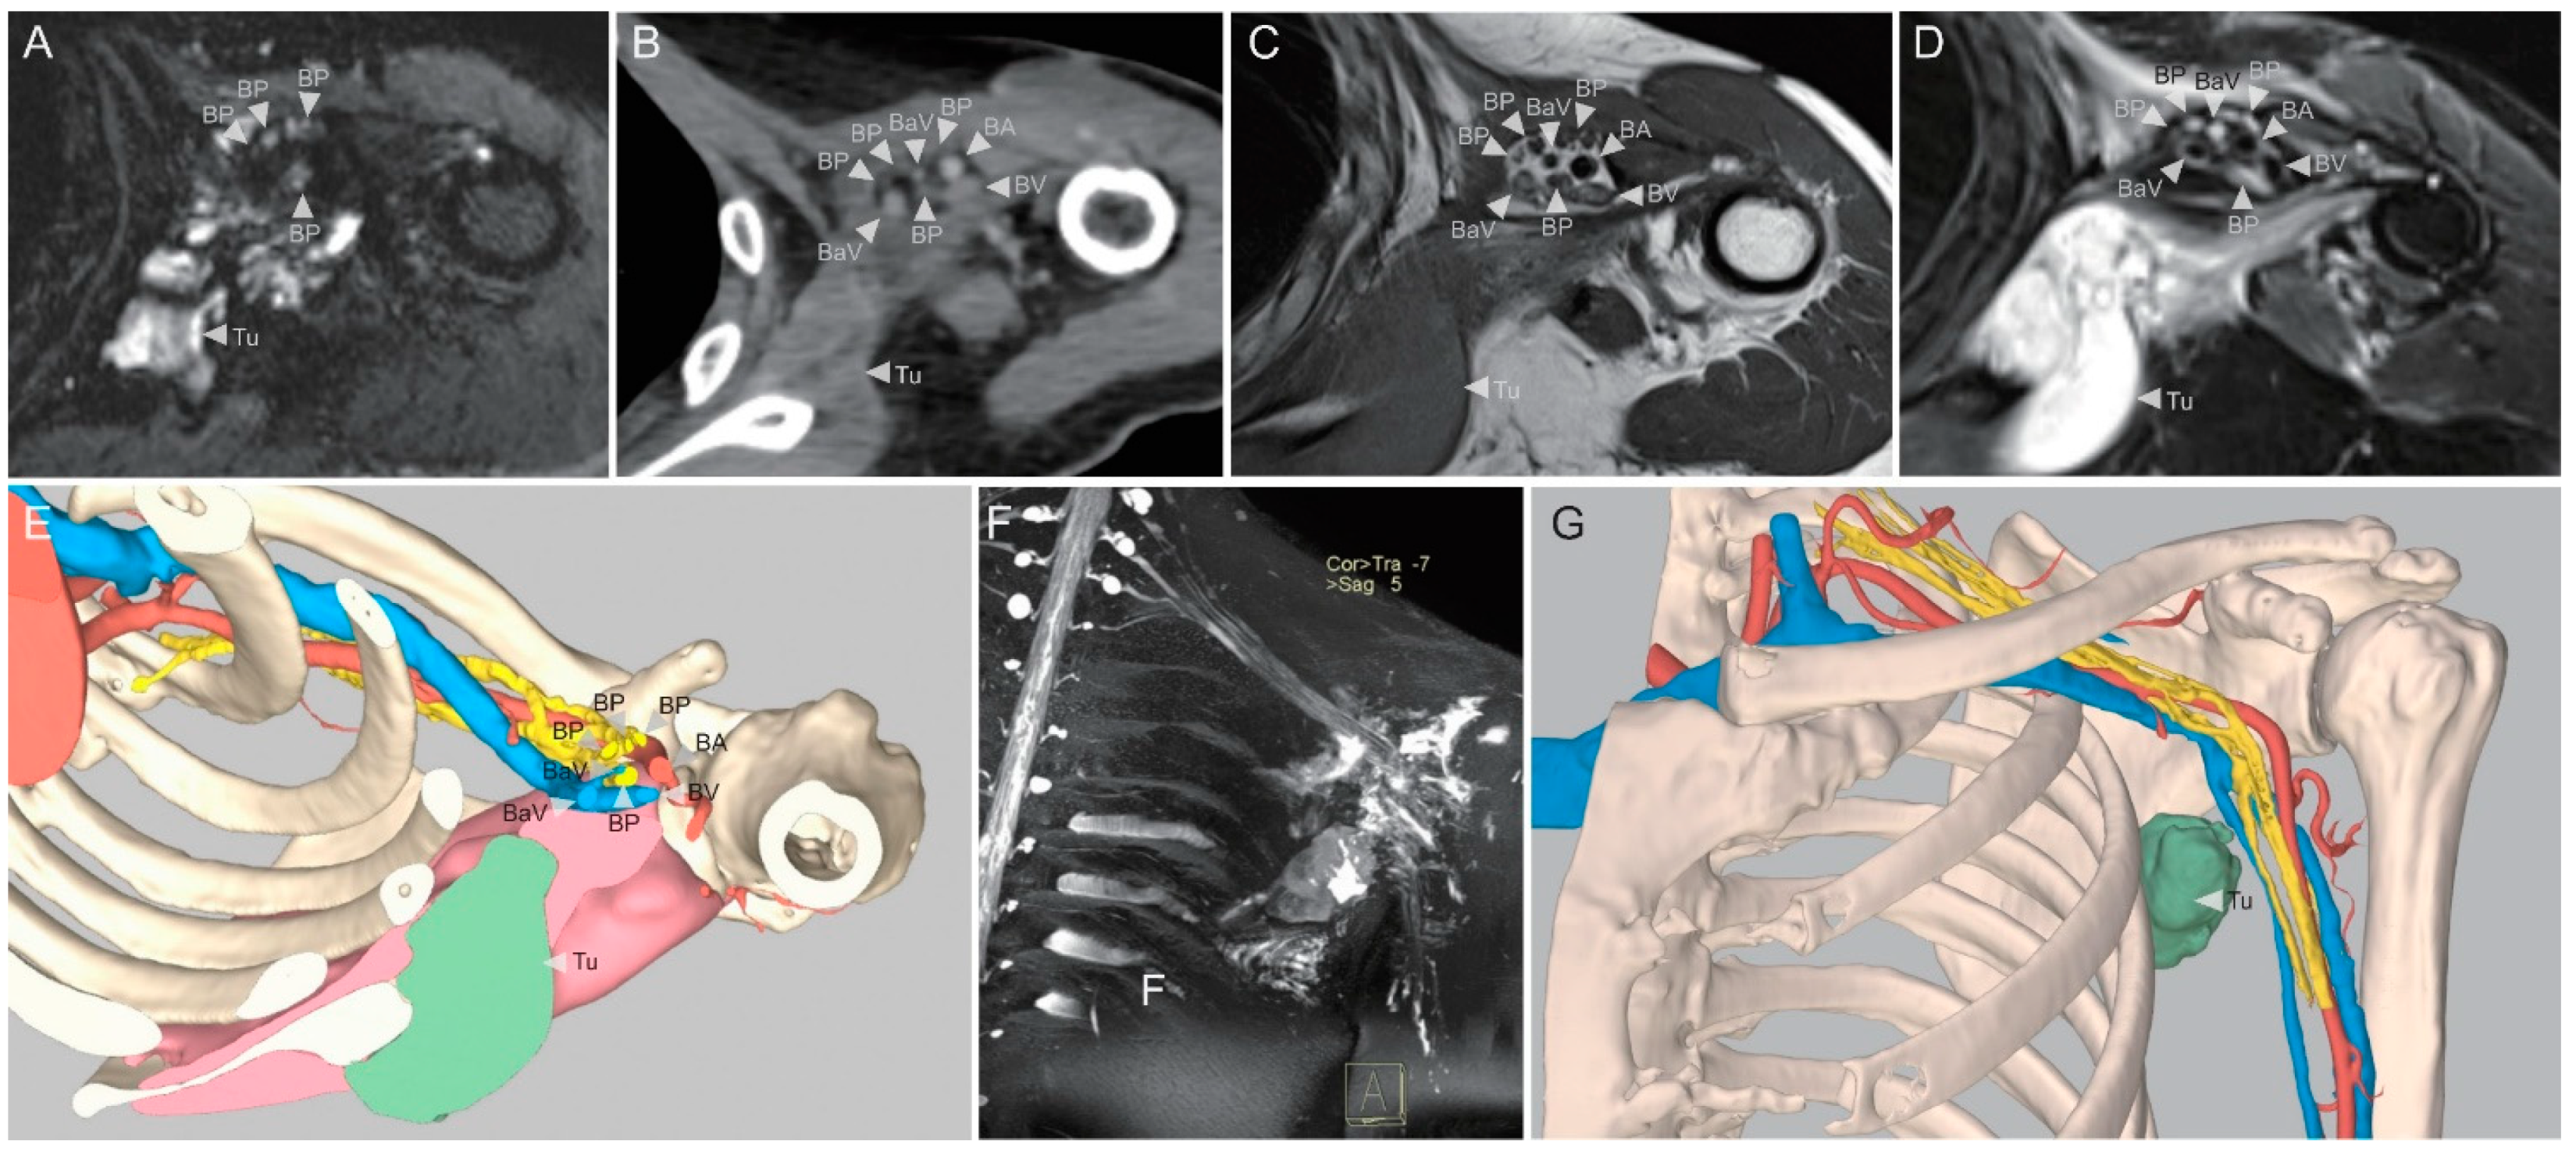

Preoperative Planning Using Three-Dimensional Multimodality Imaging for Soft Tissue Sarcoma of the Axilla: A Pilot Study

2.3. Model Preparation and Use